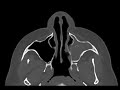

Sinus Mycetoma

These images show dense opacification of the left maxillary sinus with stippled central calcification and maxillary sinus wall osteitis. The dense material extends through the left maxillary antrum in the left frontoethmoidal recess and the left nasal cavity. The remaining sinuses are relatively clear. These are more typical features of a mycetoma given its central calcification and predominant involvement of a single sinus. Findings were confirmed on pathology which showed noninvasive aspergillus. Erosion would also be more characteristic of allergic fungal sinusitis